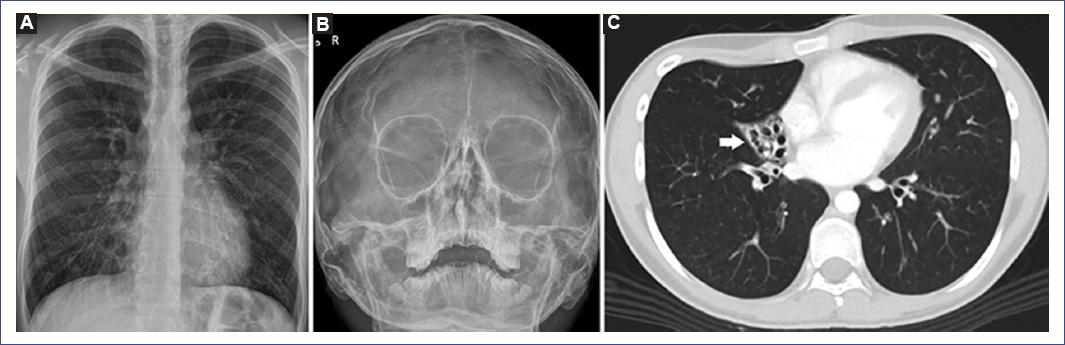

Los estudios radiológicos mostraron opacidad paracardiaca derecha que borraba parcialmente el borde cardiaco derecho y refuerzo de la trama broncovascular bilateral (Fig. 2A), alteración de los senos paranasales (Fig. 2B), bronquiectasias quísticas del lóbulo medio (Fig. 2C) y bronquiectasias cilíndricas en ambos lóbulos inferiores.

Figura 2 A: radiografía de tórax. Se observan opacidad paracardiaca derecha que borra parcialmente el borde cardiaco derecho y opacidades hiliobasales bilaterales. Además, refuerzo de la trama broncovascular bilateral. B: radiografía de senos paranasales (incidencia Waters). Se evidencia engrosamiento mucoso periférico en ambos senos maxilares con predominio izquierdo, opacificación del seno frontal izquierdo parcialmente desarrollado, seno frontal derecho aún no desarrollado y opacificación de celdillas etmoidales. C: tomografía computarizada de tórax con contraste. En corte axial en ventana de parénquima se observan bronquiectasias quísticas en el lóbulo medio (flecha).

Las mutaciones en el gen DNAI1 ocasionan alteraciones en la MET (defecto del brazo externo de dineína), el nNO (bajo) y la VMAV (mínimo movimiento), además de las características típicas como tos crónica, bronquiectasias, rinitis crónica, distrés respiratorio neonatal, defectos de lateralidad y problemas de fertilidad12. Nuestro paciente tenía un fenotipo típico de DCP (PICADAR 8 puntos)6, bronquiectasias cilíndricas basales bilaterales y del lóbulo medio (Fig. 2), y en la MET mostró alteraciones ultraestructurales compatibles con DCP (Fig. 3); esto último podría correlacionarse con la alteración del gen DNAI1 encontrada en el estudio genético.